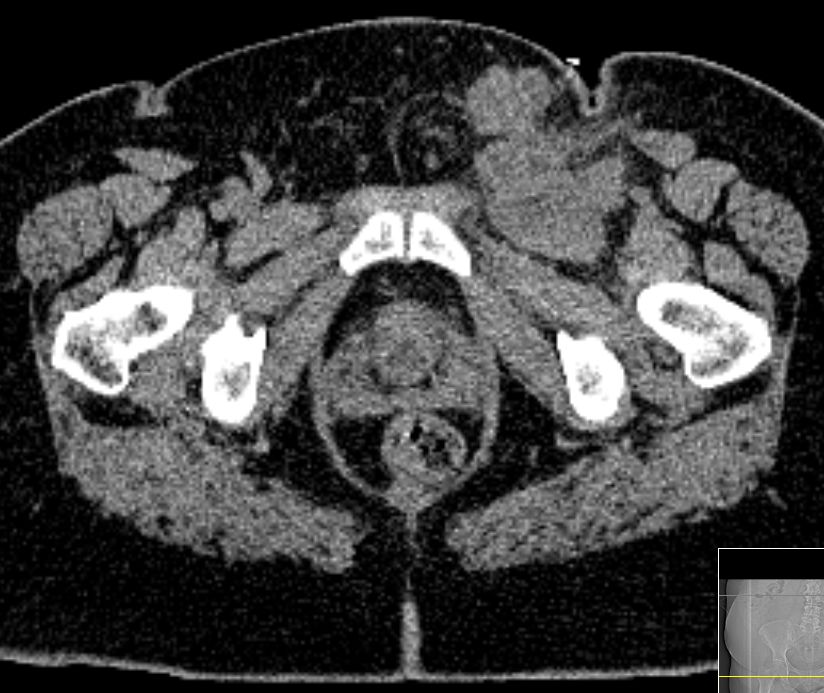

CT

61-jährige Frau mit Adipositas, Diabetes mellitus,  Hypertonie, Cholezystektomie. Vor 2 Jahren Vulva-Karzinom pT1b pN1b (1/24) M0 G2 . Vulvektomie rechts, Hemivulvektomie links mit, Sentinel-Lymphonodektomie inguinal bds. Vor 4 Monaten Lymphknotenmetastase links, R2 - Resektion, Bestrahlung abgelehnt. Jetzt progrediente Leistenmetastasierung.